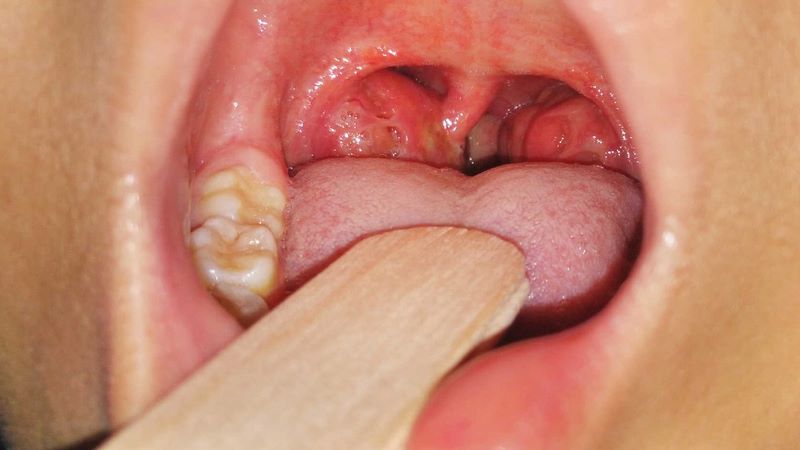

- Amidan nằm ở hai bên thành họng dưới, có chức năng bảo vệ cơ thể chống lại vi khuẩn và virus xâm nhập qua đường miệng. Khi amidan viêm nhiều lần trong năm, quá phát hoặc có tổn thương như áp xe, sỏi amidan, bác sĩ có thể chỉ định cắt amidan.

Cắt amidan và nạo VA khác nhau về vị trí, kỹ thuật và chỉ định y khoa. Tuy nhiên, trong một số trường hợp, bệnh nhân có thể cần thực hiện đồng thời cả hai phương pháp nếu cả amidan và VA đều quá phát hoặc viêm tái đi tái lại.